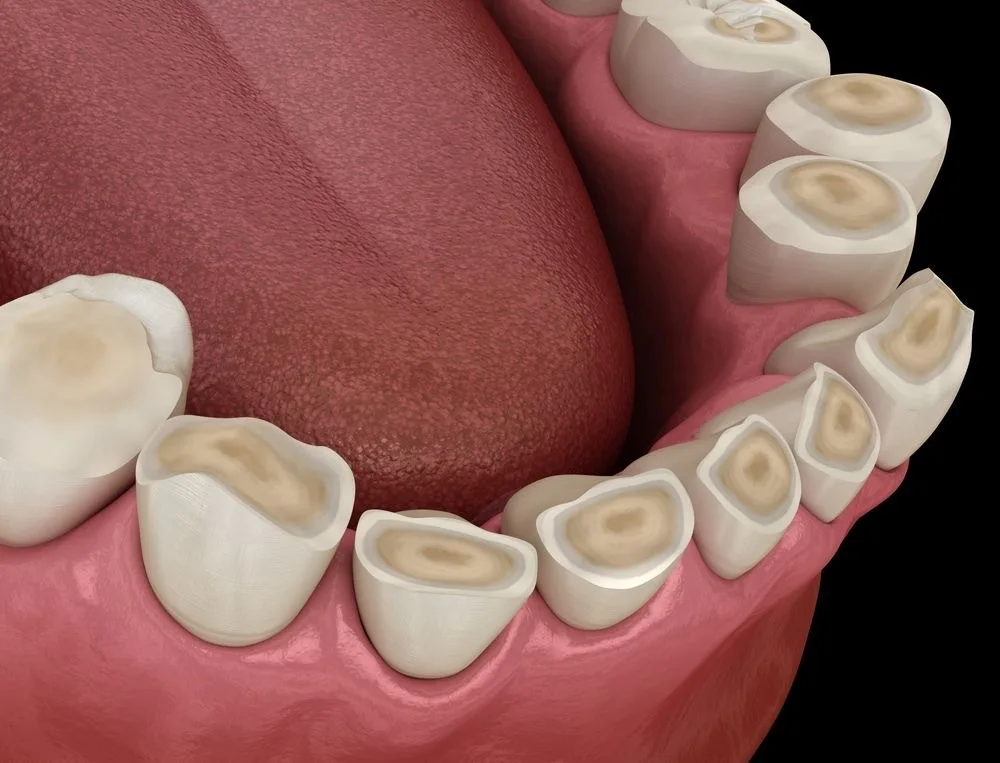

Predstavlja proučavanje, dijagnostiku i sveobuhvatno lečenje zuba kako bi im se vratila predhodna funkcija i estetika. Nakon dugotrajnog nagomilavanja dentalnog plaka (hrane), na zubima dolazi do stvaranja karijesne lezije koja prouzrokuje bolove i neprijatan osećaj u usnoj duplji. Potpunim uklanjanjem karijesne lezije, postavkom savremenih restaurativnih materijala (plombe) zubu se vraća estetski oblik kao i prvobitna funkcionalnost stomatognatnog sistema.